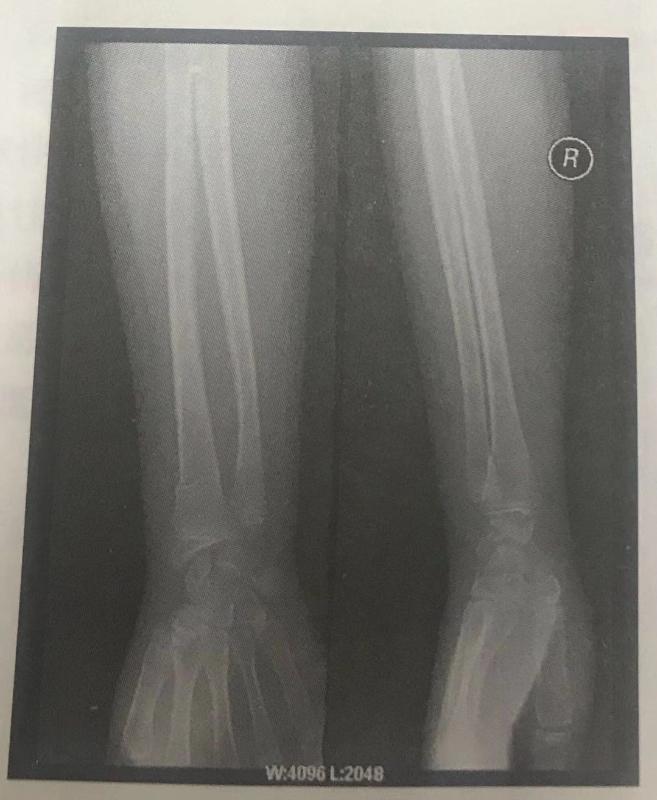

西医答辩例题1:根据下面X线片判断临床意义。(5分)

【本题 5 分,建议 1 分钟内完成本题】

【正确答案】 参考答题要点:右挠骨远端青枝骨折。

【该题针对“X线片”知识点进行考核】